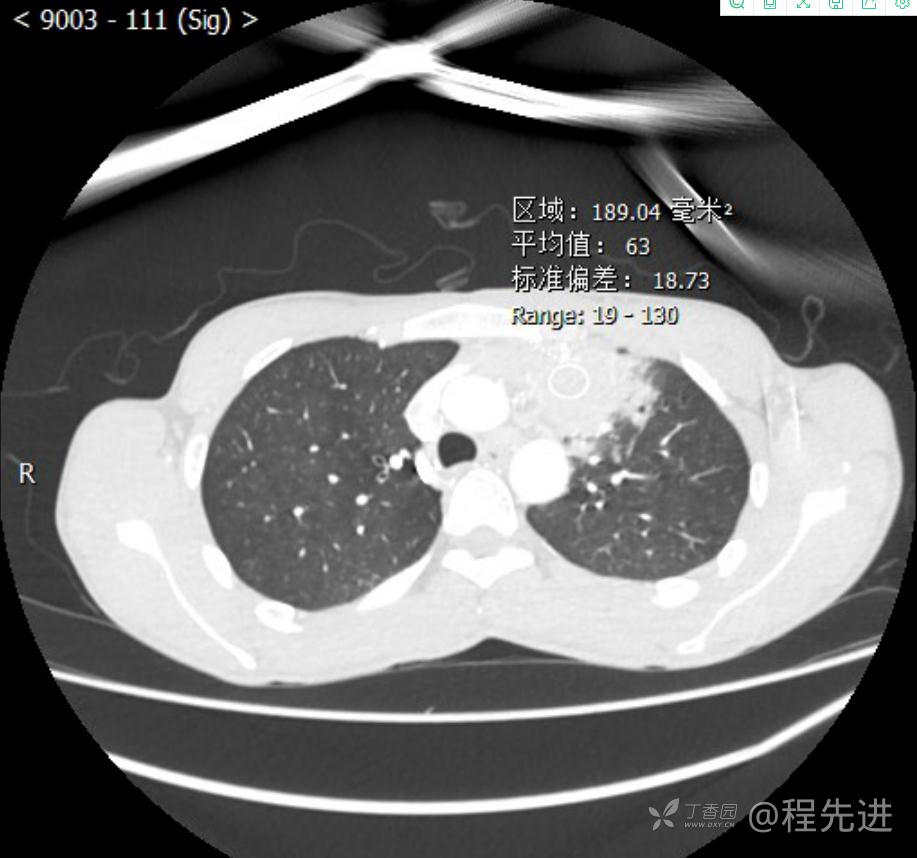

主诉:反复咳嗽1月,发现“纵隔”占位半月,乏力10余天。

现病史:患者1月前无明显诱因出现咳嗽,以夜间为著,伴有少量白痰,无发热,无胸痛、咯血,无痰中带血,未予重视,半月前外院行胸部CT检查发现“左前上纵隔”占位,未予进一步检查及治疗。近10余天自觉乏力,逐渐加重。